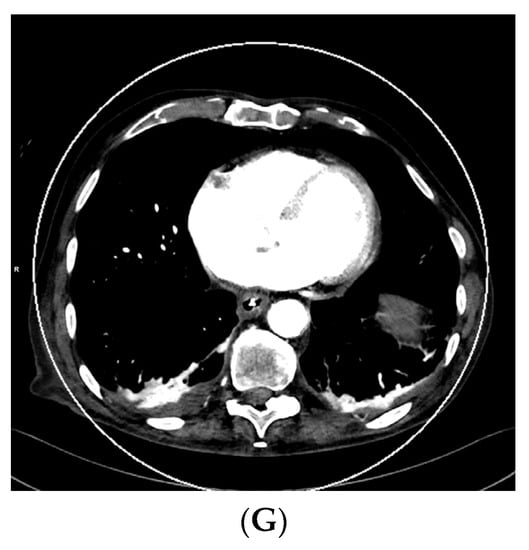

As vascular applications were one of the first fields where the benefits of DECT were demonstrated in studies and applied to routine clinical practice, aortic imaging is one of the essential fields in this context. Using DECT, it is possible to explore the effect of low-kV acquisitions using the K-edge of iodine for improved contrast in series. Martin et al. (2017), Albrecht et al. (2016), and others described that enhanced iodine contrast allows for improved detection of endoleaks; for example, in the context of thoracal or abdominal endovascular aortic repairs thoracic endovascular aortic repair (TEVAR), endovascular aneurysm repair (EVAR), fenestrated endovascular aneurysm repair (FEVAR), as well as insufficiencies and leakage of surgically implemented grafts [17,51,52,53]. Furthermore, this technique can compensate for the missed bolus and insufficient concentrations of iodine to a certain degree. The literature described that the contrast agent amount could be reduced by up to 50% in the vasculature by using 50 kV reconstructions [26]. This could be especially relevant to patients with impaired renal function, which is often associated with generalized vascular disease; however, the low-kV images also have more image noise owing to the higher rate of interaction of the photons with the atoms of the scanned body, which varies in severity depending on the DECT hardware used [6]. Figure 1 shows a case of low intravascular iodine contrast, which was caused by low-output cardiac function, as seen in the VMI reconstruction at 120 kV (Figure 1A).

Figure 1.

Acquisition of a DECT CTA of the thoracic aorta with a bad intravascular contrastation due to low output cardiac insufficiency in a 75-year-old male patient suffering from chest pain, tachycardia, and peripheral edema; (A) shows an axial view 120 kV VMI reconstruction of the descending aorta thoracalis with low intravascular contrast. Further, we see bilateral pleural effusions with adjacent partial atelectasis of the lung parenchyma. Aortic dissection could be ruled out as a cause for the clinical presentation; (B–G) show monoenergetic VMI reconstructions from 40 to 90 kV in 10 kV steps, with increasing contrast from the higher kV reconstruction of 90 kV (B) to the low-kV reconstructions with maximum intravasal contrast in the 40 kV reconstruction (G), which is closest to the K-edge of iodine, which is located at 33 kV. Accordingly, the K-edge peak is found in (G), as the highest intravasal attenuation is found here.

Consequently, VMI reconstruction was used to optimize intravascular contrast by generating monoenergetic reconstructions from 40–90 kV in 10 kV steps (Figure 1B–G, with the maximum contrast visible in the VMI 40 kV reconstruction (Figure 1G). This is especially important in the context of the visibility of small vessels, bleeding, and low-attenuation lesions. Furthermore, iodine mapping can be used to prove the accumulation of extravasal iodine in hematomas and bleeding. Using mixed images, for example, 120 kV, which is calculated from the high- and low-kV images, can improve the image noise. Furthermore, it is possible to create virtual unenhanced images or use other material-specific applications that are derived from (virtual) monoenergetic images. These monoenergetic images can be reconstructed at 40–190 kV for DSCT DECT. In this context, calcium subtraction from calcified plaques is important [17,20].